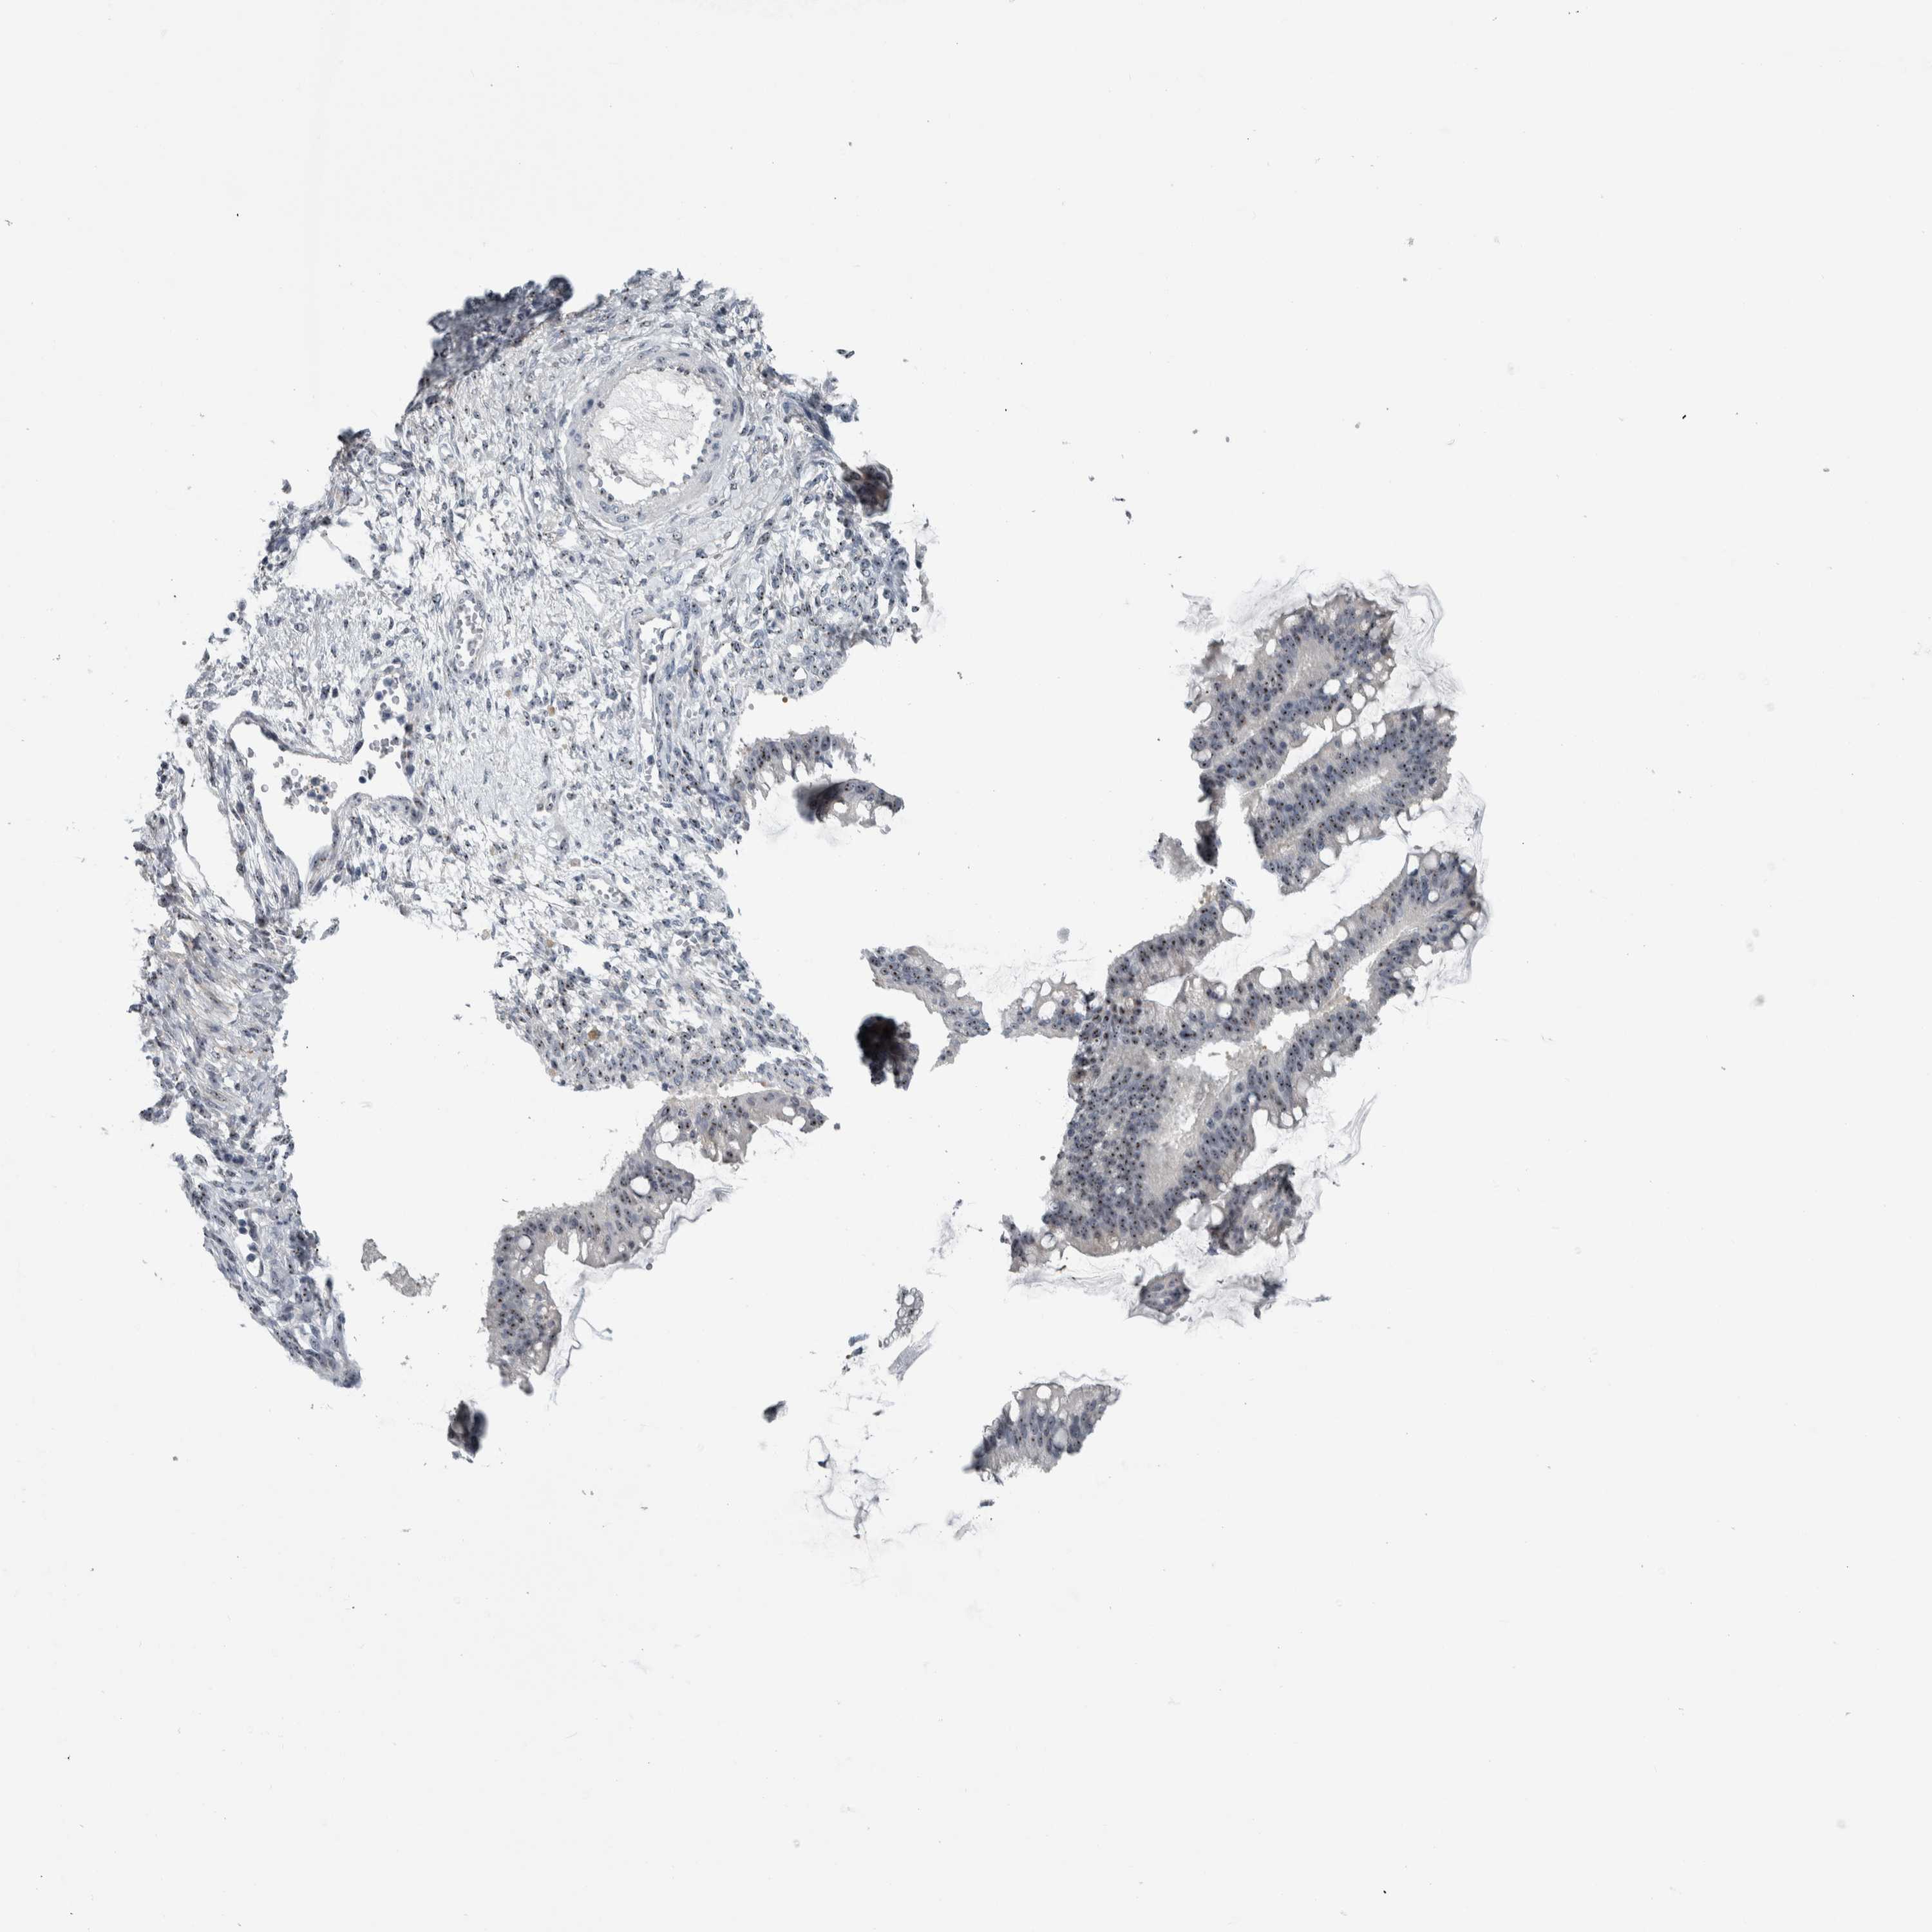

OVARIAN CANCER - Protein expressioni

A mouse-over function shows sample information and annotation data. Click on an image to view it in a full screen mode. Samples can be filtered based on level of antibody staining by selecting one or several of the following categories: high, medium, low and not detected. The assay and annotation is described here.

Note that samples used for immunohistochemistry by the Human Protein Atlas do not correspond to samples in the TCGA dataset.

Antibody stainingi

Antibody staining in the annotated cell types in the current human tissue is reported as not detected, low, medium, or high, based on conventional immunohistochemistry profiling in selected tissues. This score is based on the combination of the staining intensity and fraction of stained cells.

Each image is clickable and will lead to virtual microscopy that enables deeper exploration of all samples and also displays staining intensity scores, fraction scores and subcellular localization as well as patient and tissue information for each sample.

Antibody HPA025936

Staining

High

Medium

Low

Not detected

Intensity

Strong

Moderate

Weak

Negative

Quantity

>75%

75%-25%

<25%

None

Location

Nuclear

Cytoplasmic/membranous

Cytoplasmic/membranous,nuclear

Cystadenocarcinoma, serous, NOS

Carcinoma, endometroid

Cystadenocarcinoma, mucinous, NOS

Carcinoma, NOS